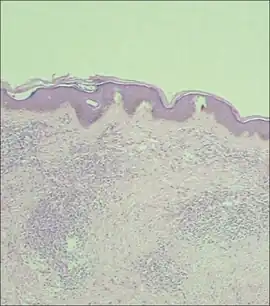

Marrow involvement is typically diffuse with morphology similar to what is observed in peripheral blood.[1] In the spleen, the leukemic cell infiltrate both the red pulp and white pulp, and lymph node involvement is typically diffuse through the paracortex.[1] Skin infiltrates are seen in 20% of patients, and the infiltrates are usually dense and confined to the dermis and around the skin appendages.[2]